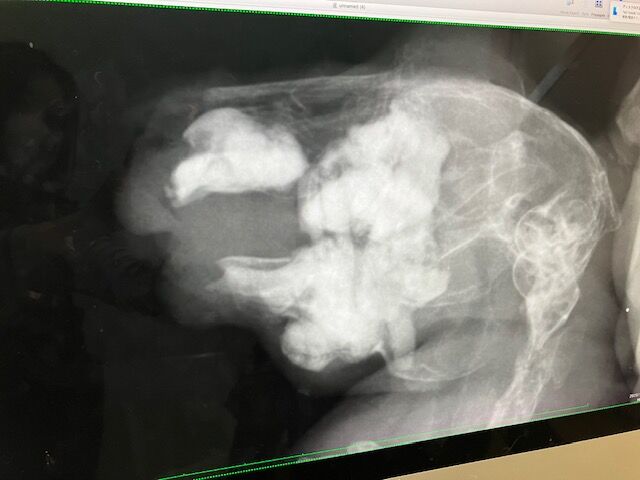

レントゲン

歯根への影響も見られず、共に良好でした